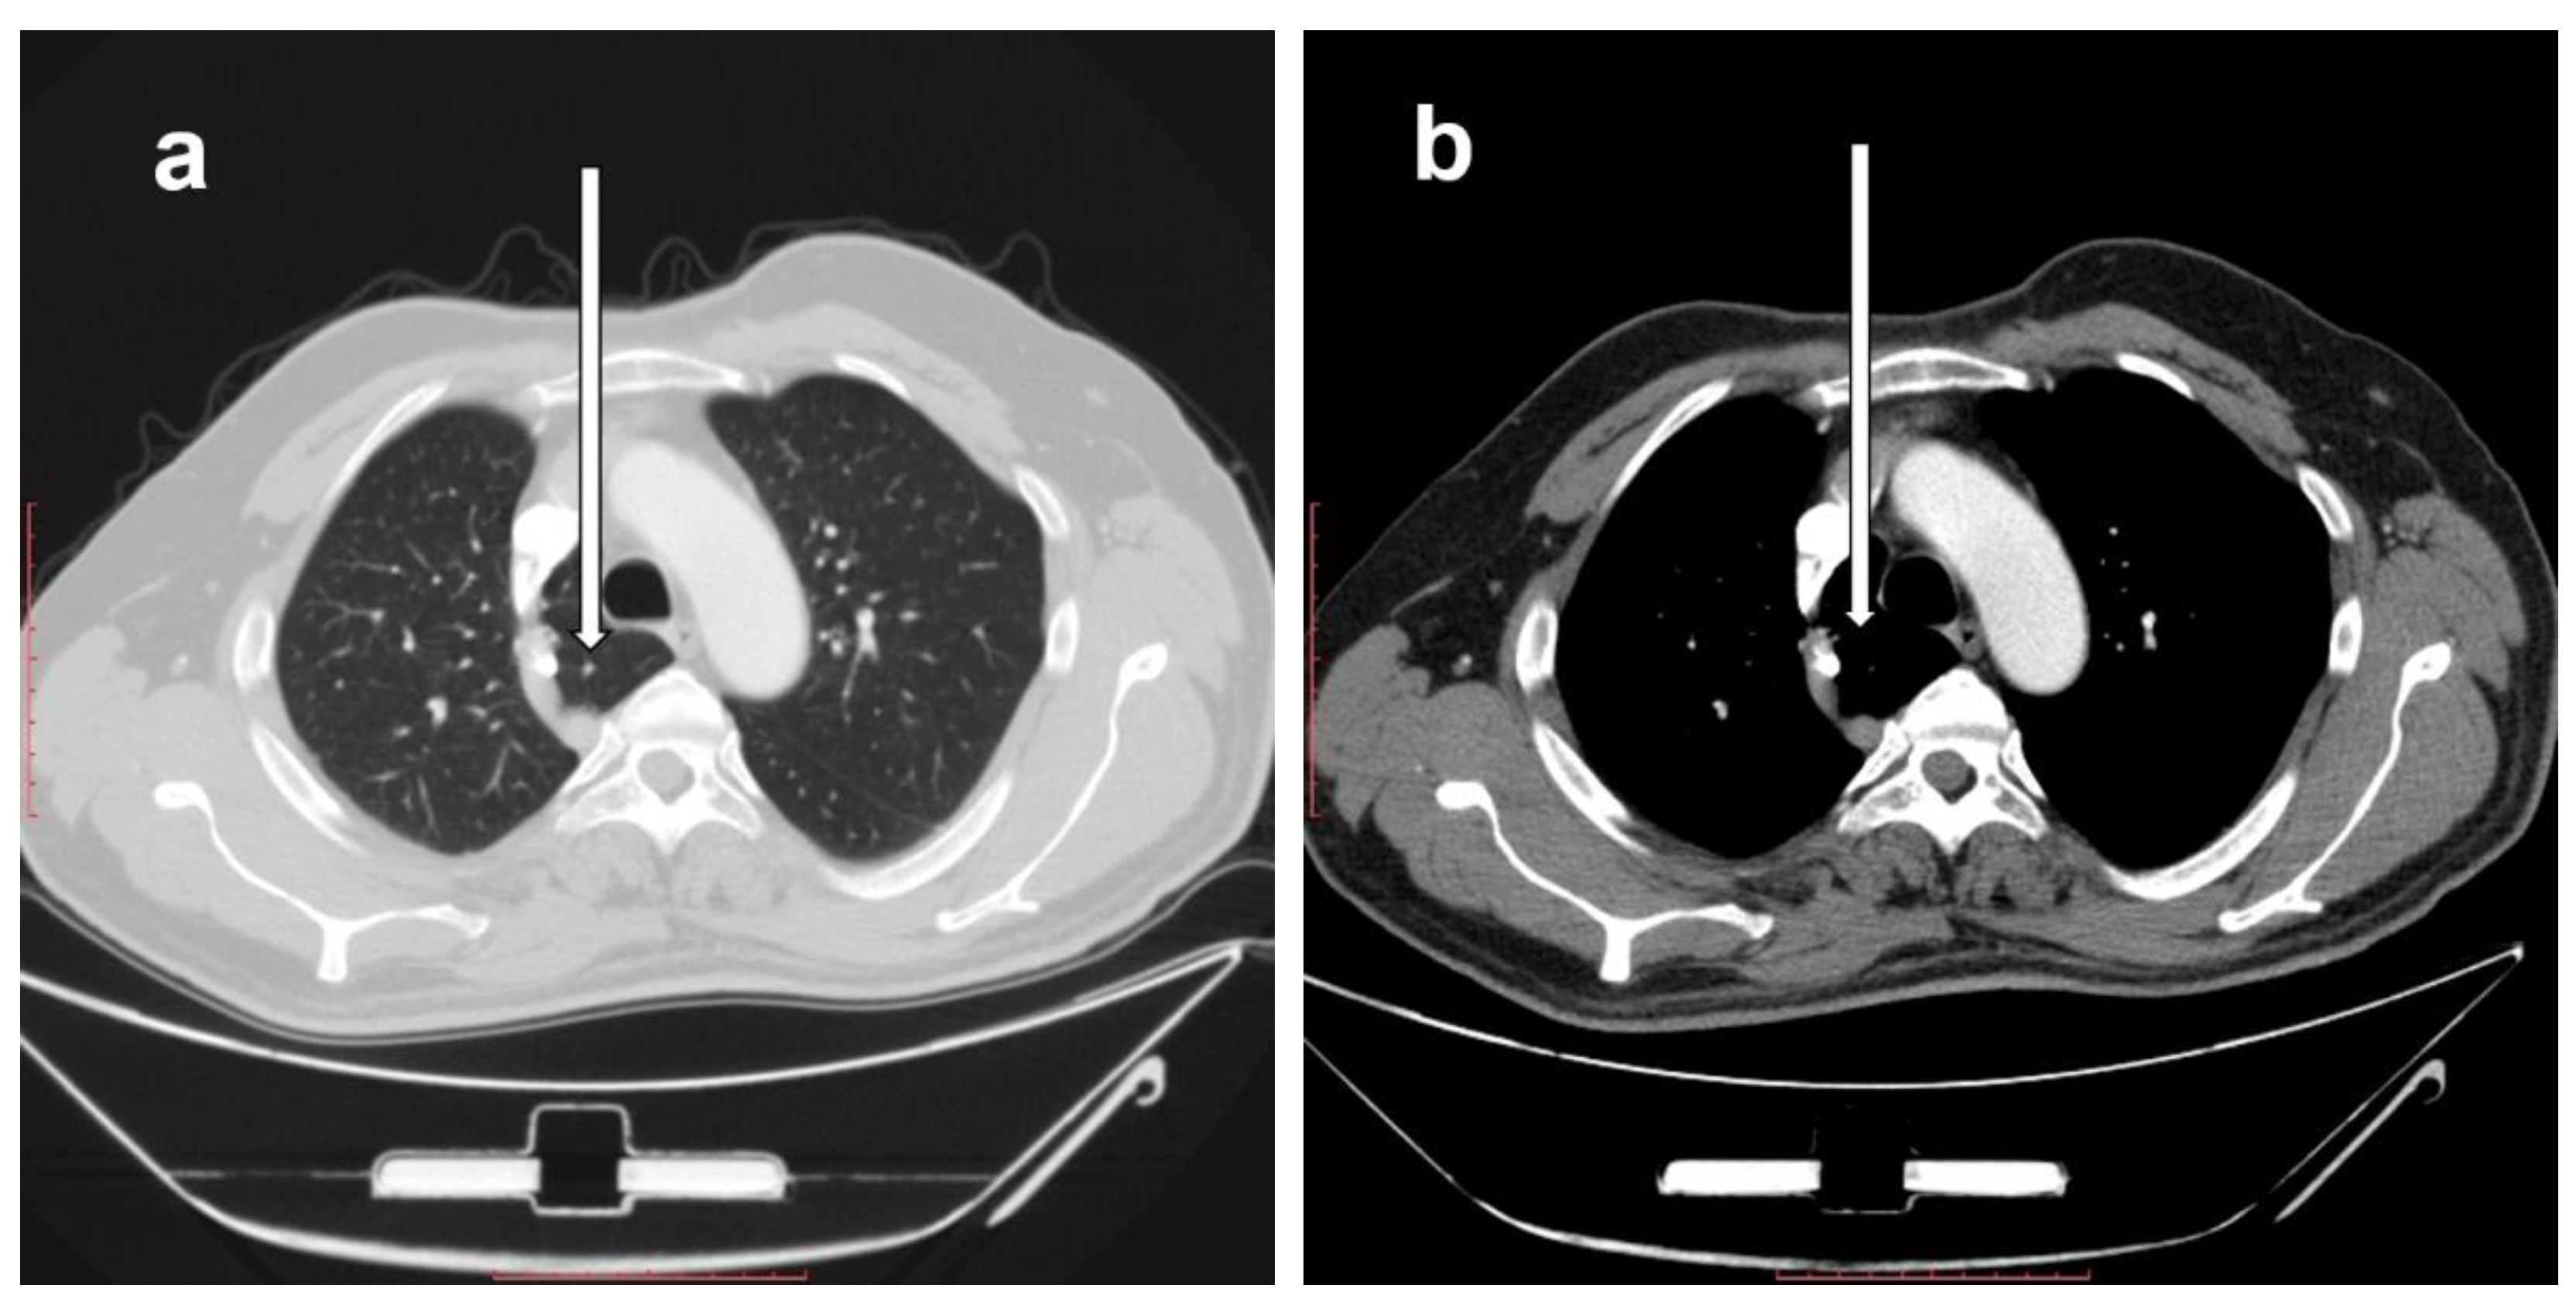

The right azygos lobe is seen in CT images of the right lung using the lung and mediastinal windows. It causes changes in the standard anatomy of the right lung-mediastinal relations. It is identified in the immediate right pre-, para-, and retro-tracheal locations by first identifying the azygos vein and arch (which is shifted superiorly in the case of an azygos lobe) and its drainage in the superior vena cava, with the azygos lobe seen in Figure 1 being inseparable from the postero-medial wall of superior vena cava. The azygos lobe is seen medial to the azygos vein, with its posterior part seen to the right of the esophagus.

Figure 1.

Axial computed tomography (CT) cuts showing the right azygos lobe (white arrows) in the same patient in a lung window (a) and in a mediastinal window (b). Scale bar = 10 cm.